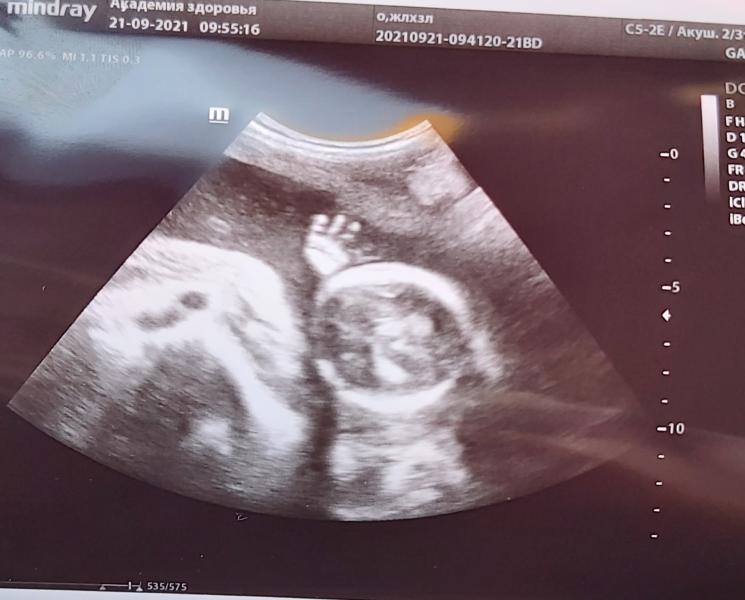

Мой мальчик!💙 Передал привет маме с папой! Мы тебя очень любим и ждем! Девочки, какая милота! Не могу!😍😍😍

Была на УЗИ, подтвердили мальчугана! Ура!🥰

Благодарю)) 💐это ещё не скрининг, это мои переживания)) то там потянуло, то заболело)) вот не удержалась и сходила на УЗИ 🤭Второй скрининг в пятницу😄

Мы все как увидели это чудо, рая без слов нажала на печать фото)) фото в рамку, однозначно!)

Это он моськой к «камере» прям повернулся что ли? Прелесть 🥰